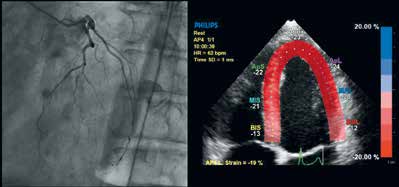

同时,心脏介入实时导航(EchoNavigator)为X线和实时经食道三维超声心动图(Live 3D TEE)之间的实时融合导航提供了自动配准和跟踪—所有步骤都可在操作台简单控制。

iXR和实时经食道三维超声心动图(Live 3D TEE)的实时融合。